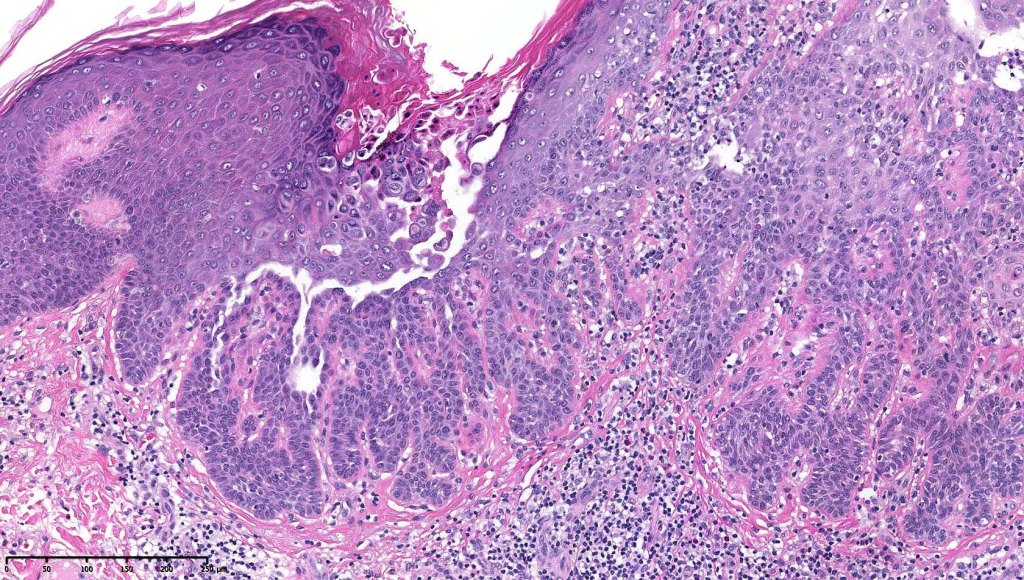

•Cup-shaped, cystic invagination containing keratinous debris showing conspicuous corps ronds & grains of Darier

•The deeper reaches show acantholysis and prominent suprabasal villi